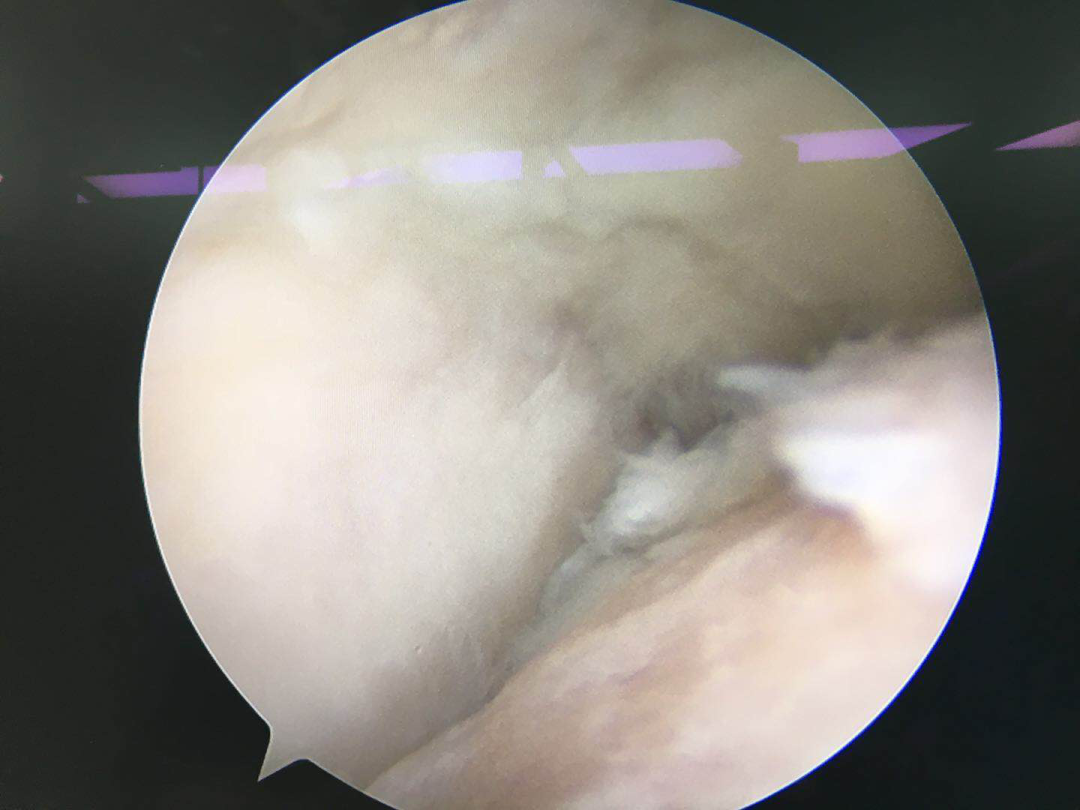

術(shù)中,在關(guān)節(jié)鏡下可見患者踝關(guān)節(jié)軟骨嚴(yán)重磨損,予關(guān)節(jié)清理并行微創(chuàng)融合。